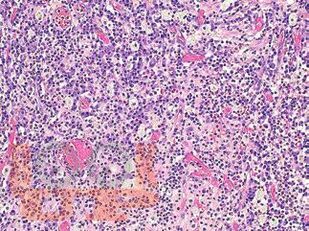

В атласе подробно изложено цитологическое и гистологическое описание всего спектра патологических изменений ткани молочной железы: неопухолевые, пролиферативные процессы, предраковые поражения, доброкачественные и злокачественные опухоли. Кратко представлены данные об этиологии, о патогенезе, молекулярной генетике, клинической картине и лучевых методах исследования различных поражений молочной железы. Подробно описаны дифференциальная диагностика и возможные ошибки морфологической диагностики. Атлас иллюстрирован большим количеством микрофотографий.

Традиционная морфология имеет фундаментальное значение в диагностической патологии. Атлас представляет собой реферативный текст, в котором обобщены имеющиеся на данный момент основные знания о патологии молочной железы, собранные из различных источников, и собственный опыт авторов. Текст построен в виде коротких фраз, постулирующих ключевые моменты различных поражений молочной железы.